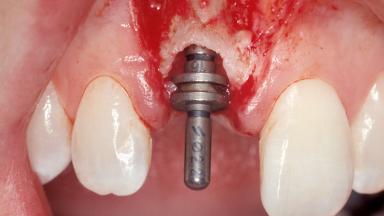

Immediate Placement of an Implant in a Maxillary Right Central Incisor Site

A 30-year-old female patient was referred to the office for the treatment of tooth 11. Her chief concern at the initial visit was to inquire, “Why is my tooth pink?” Upon clinical examination, it was determined that tooth 11 had a previous history of trauma and that the clinical crown had become noticeably pink in color as a result of internal resorption. This diagnosis was confirmed radiographically, indicating a large radiolucency involving the central and distal portions of the clinical crown. It was determined that restoration of this tooth was not possible, and that extraction was indicated. The presence of a mid-line diastema, which the patient wanted to reproduce, directed the treatment plan for tooth replacement utilizing a dental implant.

Placement Protocol Immediate implant placement

Tooth Site Maxillary incisor or canine

Socket Morphology Single-root socket

Socket Integrity Sufficient, with intact bone walls